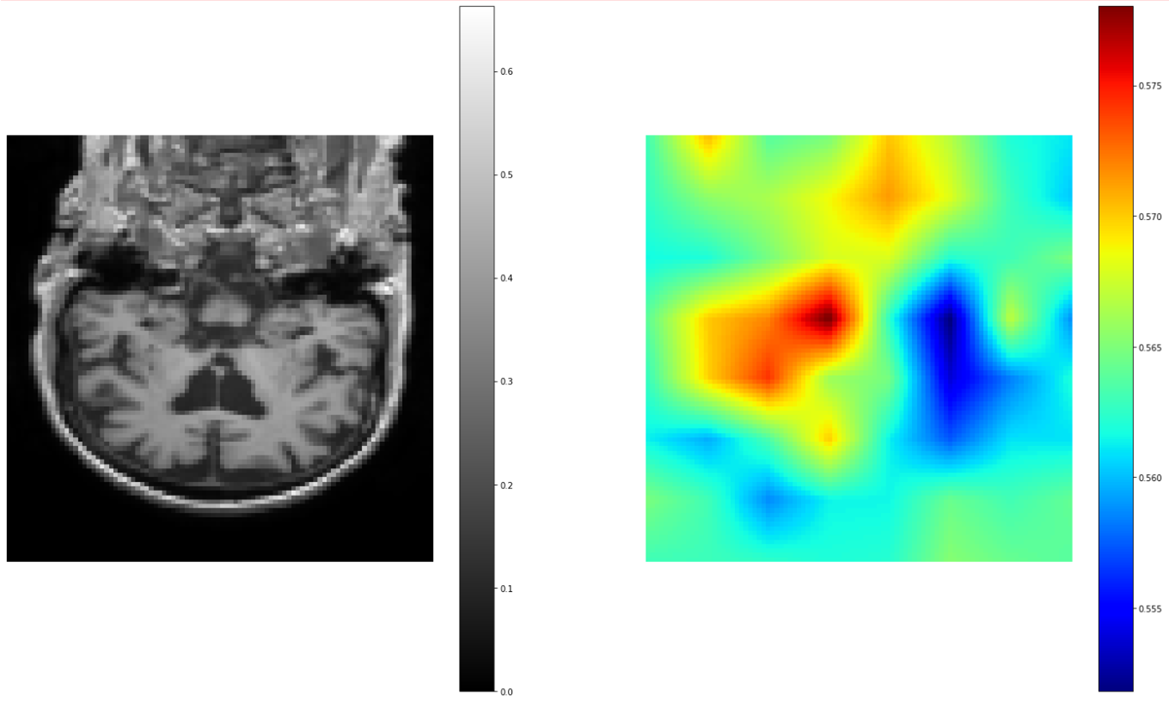

可视化模型决策依据:遮挡敏感度分析

训练完成后,我们不仅关心模型“对不对”,还想知道它“为什么对”。我们加载最佳模型,并使用遮挡敏感度技术来可视化模型在进行分类时,最关注大脑的哪些区域。

model.load_state_dict(torch.load("best_metric_model_3d.pth")) # 从验证集中取一个样本 img, label = val_ds[0] img = img.unsqueeze(0).to(device) # 初始化遮挡敏感度分析器 occ_sens = monai.visualize.OcclusionSensitivity(nn_module=model, mask_size=12, n_batch=10) # 为节省时间,我们只分析中间一个切片的热力图 depth_slice = img.shape[2] // 2 occ_sens_b_box = [depth_slice - 1, depth_slice, -1, -1, -1, -1] # 运行分析 occ_result, _ = occ_sens(x=img, b_box=occ_sens_b_box) # 获取对应正确类别的热力图 true_label_index = label.item() occ_result_slice = occ_result[0, true_label_index] # 绘图 fig, axes = plt.subplots(1, 2, figsize=(12, 6)) axes[0].set_title("Original MRI Slice") axes[0].imshow(img.cpu().numpy()[0, 0, depth_slice, :, :], cmap="gray") axes[0].axis("off") axes[1].set_title("Occlusion Sensitivity Heatmap") im = axes[1].imshow(occ_result_slice.detach().cpu(), cmap="jet") axes[1].axis("off") fig.colorbar(im, ax=axes[1]) plt.show()